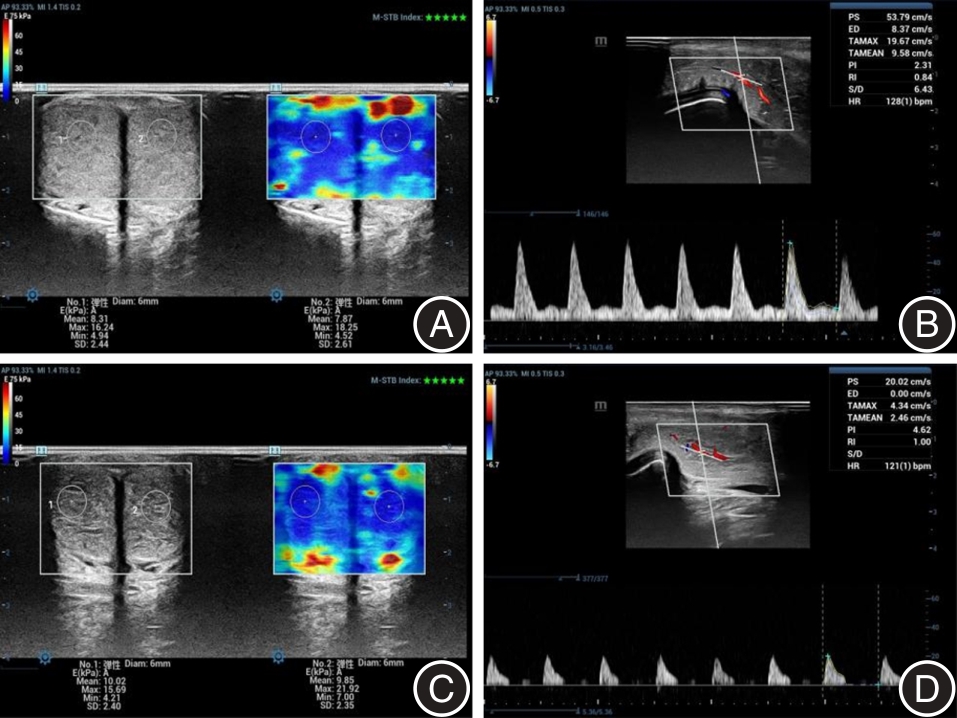

Objective To assess the utility of real?time shear wave elastography (SWE) in diagnosing vascular erectile dysfunction (ED) and to predict the optimal timing for color Doppler flow imaging (CDFI) examination. Methods Patients diagnosed with ED who received intracavernosal injection (ICI) of vasoactive drugs were recruited and categorized based on CDFI findings into three groups: arterial ED (n = 17), venous ED (n = 33), and non?vascular ED (n = 29). SWE technology was utilized to measure the average Young's modulus (E value) of the corpus cavernosum in these patients, both in the flaccid state prior to ICI and at four time points following ICI?induced erection. Subsequently, the differences in E values among the three groups were analyzed. Results There was no significant difference in the E value of the corpus cavernosum in the flaccid state among the arterial, venous, and non?vascular ED groups before ICI (P > 0.05). However, the E value in the flaccid state for each group was significantly higher than the mean E values observed at the four time points after ICI?induced erection (P < 0.01). Additionally, the mean E values at these four time points post?ICI were also statistically significant (P < 0.01). ROC curve analysis revealed that the AUC for diagnosing arterial, venous, and non?vascular ED using the E value after ICI were 0.814, 0.770, and 0.711, respectively, with corresponding cutoff values of 9.98, 8.16 and 7.06 kPa. The combined use of CDFI and SWE cutoff values following ICI?induced erection significantly shortened the detection time for both arterial and venous ED groups (P < 0.01). Conclusions SWE can accurately measure the E value of the corpus cavernosum following erection induced by the vasoactive drug ICI, thereby facilitating the differentiation of various types of ED. Additionally, when combined with CDFI, this technique can reduce the time required for examination.